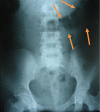

Case presentation: We describe the case of an 18-year-old Middle Eastern Caucasian woman with trichotillomania who presented to our emergency department with a history of central abdominal pain associated with vomiting and constipation for five days. An examination showed a trichobezoar requiring emergent surgical intervention, and indicating the need for psychiatric treatment. The trichobezoar was treated successfully by laparotomy.